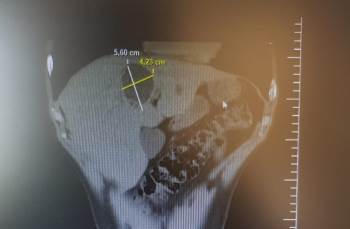

Bilecik Devlet Hastanesinde tedavi altında bulunan Sadık Akşehir (40) hasta karaciğer kist hidatik (hayvan kisti) kapalı kist ameliyatı (laparoskopik kistektomi) oldu. 5,60 ile 4,23 santimetre çapındaki kist 3 saatlik bir ameliyatın ardından alınarak, hasta 3 gün taburcu edildi. Hasta eski sağlığına kavuşurken, ameliyatı yapan Genel Cerrah Uzmanı Op. Dr. Süleyman Deniz Kahraman’a teşekkür etti.